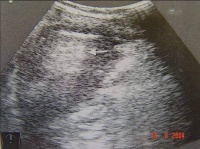

②B型超声检查:

Bk8b4.jpg

脾被摸下破裂

脾真性破裂

B超(左起图1脾中央破裂图2脾被摸下破裂图3脾真性破裂右图胃肠破裂穿孔)检查具有经济方便、可在床边检查、可重复进行动态观察、无创无痛、以及诊断准确率高等优点,因此其在腹部损伤的诊断中倍受重视.应用越来越广泛。 对肝、脾、肾等实质性脏器损伤,B超检查的确诊率达90%左右。可发现直径1— 2cm的实质

血肿,并可发现脏器包膜连续性中断和实质破裂等情况。超声检查对腹腔积液发现率很高。并可根据B超检查估计出腹腔积液的量,即每lcm液平段,腹腔积液约有500ml。由于气体对超声的反射强烈,其在声像图上表现为亮区。因此,B超检查也可发现腹腔内的积气,有助于空腔脏器破裂或穿孔的诊断。

急性胃穿孔。左叶肝前方见气体强回声